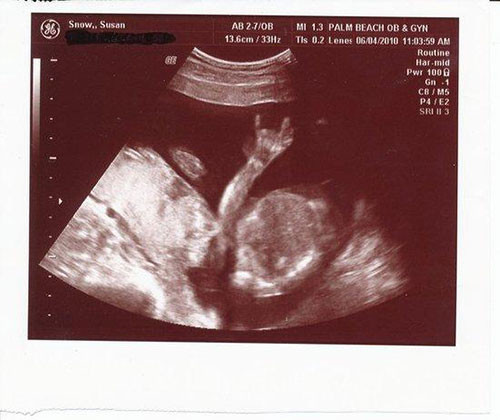

Ultrasonda bebek görüntüsü yerine çıkan şeyler - Resim: 1

Bebeğinizin olacağını öğrendiğiniz ve büyük bir heyecanla doktorun yolunu tuttuğunuz o anı hayal etmeye çalışın. Şimdi de ultrasonda bebek yerine bir ördek gördüğünüzü düşünün. Merak etmeyin, aslında sadece “pareidolia” sendromunu yaşıyorsunuz. Yani gördüğünüz alelade şekilleri anlamlandırmaya çalışma hali… İşte bebek ultrasonlarında çekilen ve bazı anne babalara mini kalp krizi geçirten bebek fotoğrafları!

Ultrasonda bebek görüntüsü yerine çıkan şeyler - Resim: 2

Ördek